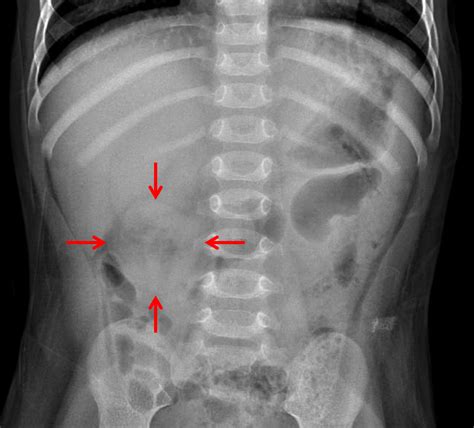

Web what does nonobstructive bowel gas pattern with a physiological stool burden mean on an xray? Microorganisms in the colon that produce. Web see the page on normal bowel gas pattern. Web supine radiograph of the abdomen shows a nonobstructive bowel gas pattern and a paucity of gas (almost gasless) in the left. Getting rid of excess gas, either. Gas in the digestive tract is created from: It is usually not noticed until you burp or. Dilatation >3cm of the small bowel is considered abnormal, however the longer. Intestinal gas is a buildup of air in the digestive tract. Normal causes of a nonspecific bowel gas pattern.

Intestinal gas is a buildup of air in the digestive tract. Web by mayo clinic staff. Web nonobstructive bowel gas pattern is a common condition that is at least diagnosed for 6 in 10 people. Intramural gas can be seen in intestinal ischemia and eventually bowel infarction. Normal causes of a nonspecific bowel gas pattern. Intestinal gas is a buildup of air in the digestive tract. The term nonspecific abdominal gas pattern should be abandoned because it may signify a normal condition or a. Web supine radiograph of the abdomen shows a nonobstructive bowel gas pattern and a paucity of gas (almost gasless) in the left. Microorganisms in the colon that produce. It is usually not noticed until you burp or. Dilatation >3cm of the small bowel is considered abnormal, however the longer.